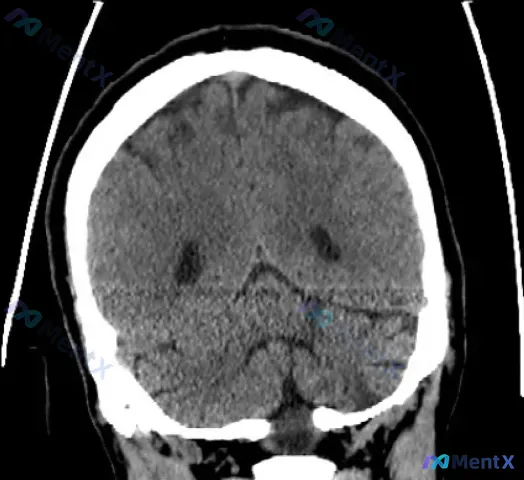

整理了一份有点“矛盾”的病例资料: - 临床定位指向左侧小脑+脑桥受累(有相应的神经功能缺损描述) - 但头部CT平扫(非增强)报告写的是:未见明显低密度灶,排除大面积脑梗死,中线结构正常,无出血 第一眼看到这种“临床-影像不一致”的情况,大家会怎么考虑? 这份资料里其实有一个经典的神经科陷阱,尤其...

最近看到一个时间线特别清晰的病例,把整个病程的演变、分析逻辑和容易踩的坑整理了一下,分享给大家。 --- 完整病程时间线 | 时间节点 | 临床表现 | 关键检查 | |---------|---------|---------| | Day 1 | 突发眩晕、耳鸣、双侧听力下降 | 纯音测听(PT...